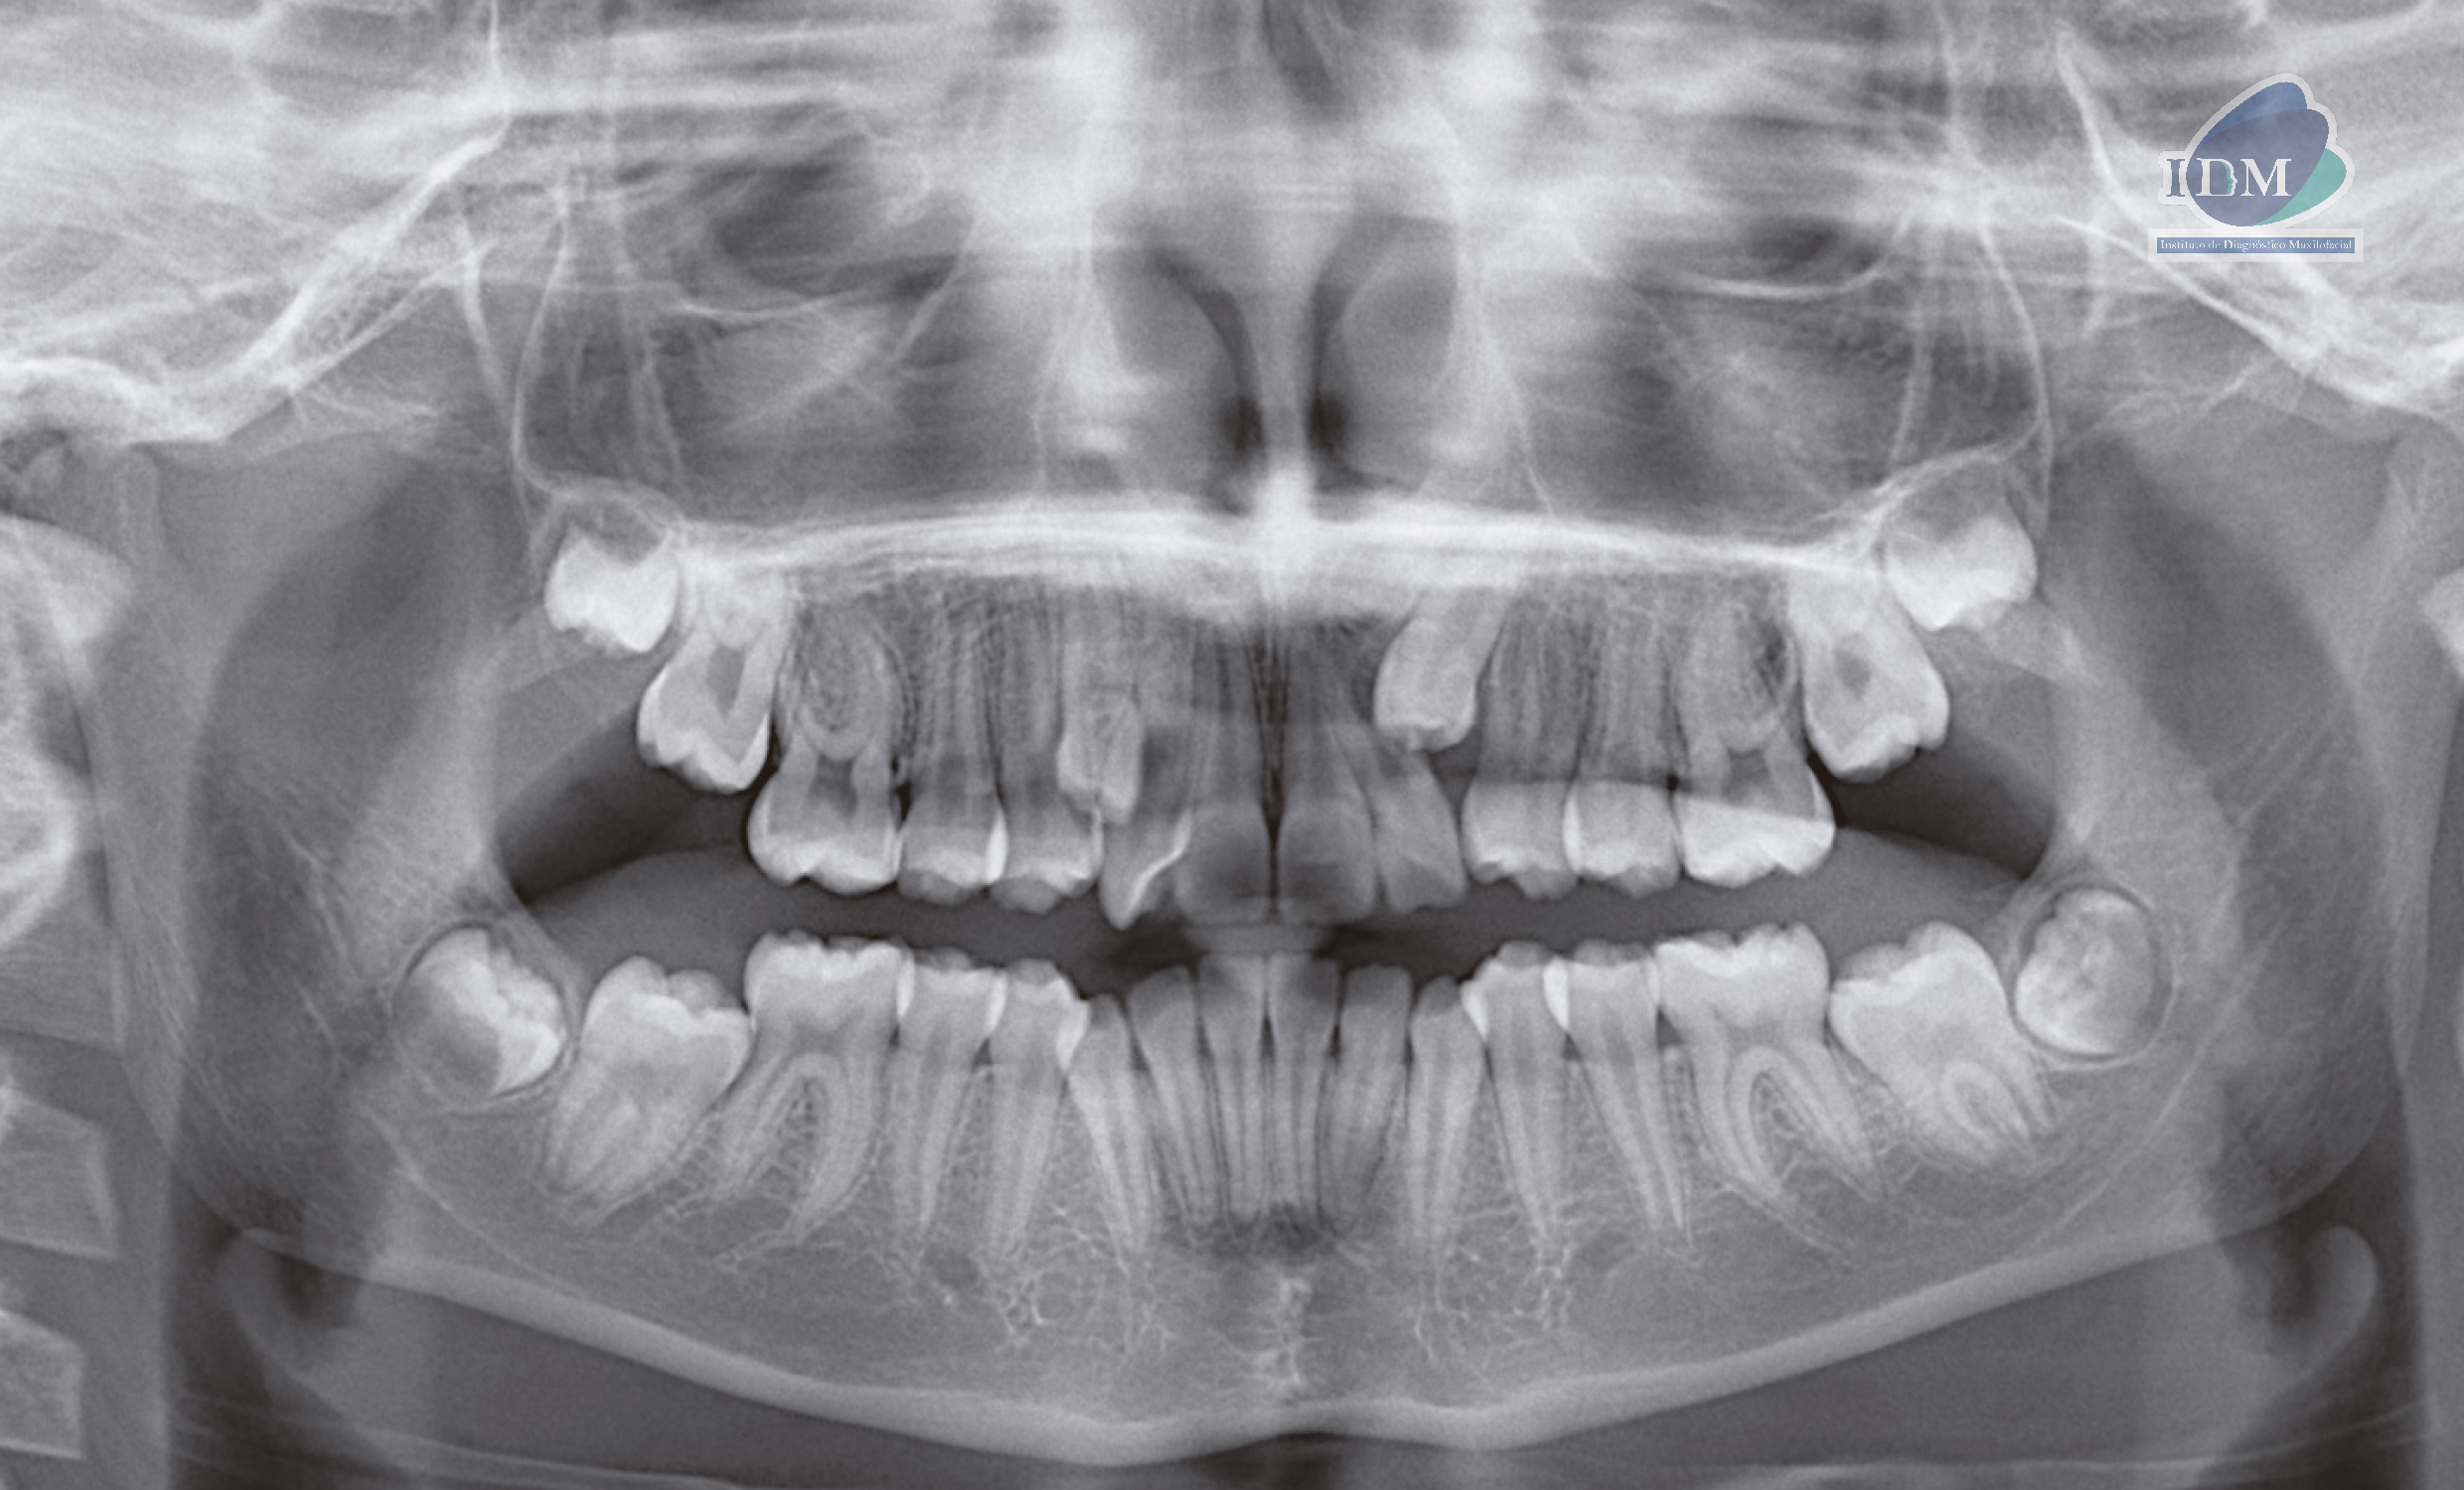

Radiografia Panorámica

A la evaluación de la radiografía panorámica se observa terceras molares en evolución intraósea, piezas dentarias 18 y 28 en evolución extraósea y distoanguladas; piezas 37 y 47 en evolución extraósea y mesioanguladas; asimismo se observa la 13 en evolución extraósea en posición ectópica y la pieza 23 mesioangulada e impactada.